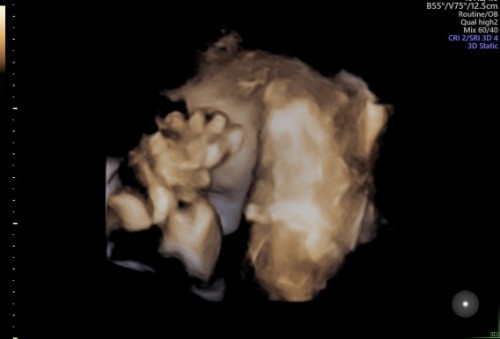

Semalem abis USG,karna kepala dd udah di bawah jadi susah buat liat mukanya,oiya usia kehamilan 35weeks . Jadi pas periksa semalem itu pas di tensi tumben banget tensinya tinggi,jadi pas diperiksa sama Dokternya ,kaya gimana gitu muka dokternya,pas ditanya semua2 nya udah normal,cuma tensi ku tinggi takut ngaruk ke janin,aku jadi kepikiran dan khawatir 🥺 ini anak ke 3 aku,yang 1 dan 2 keguguran ,jadi bener2 pas denger dokter bilang gitu aku kepikiran .#seriusnanya #bantusharing #pleasehelp #firstbaby #First_Baby #first